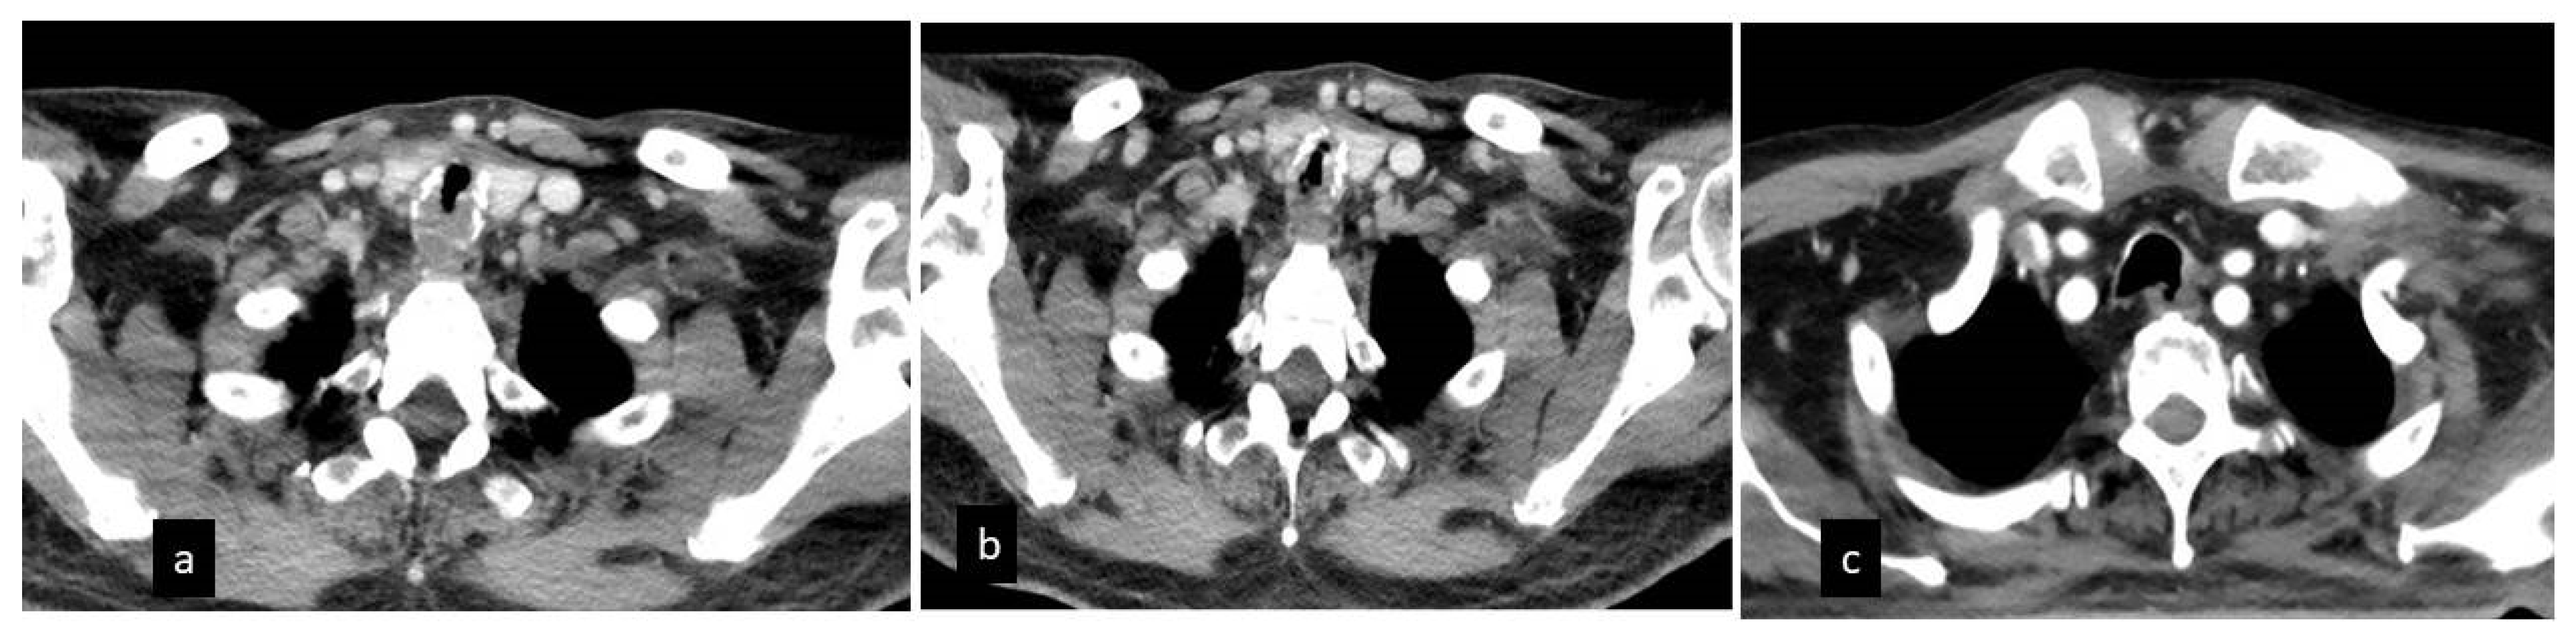

| Evidence tracheal cartilage fracture in the CT | 19/23 (82.6%) |

| Evidence of residual bilateral ground glass opacities | 13/23 (56.5%) |